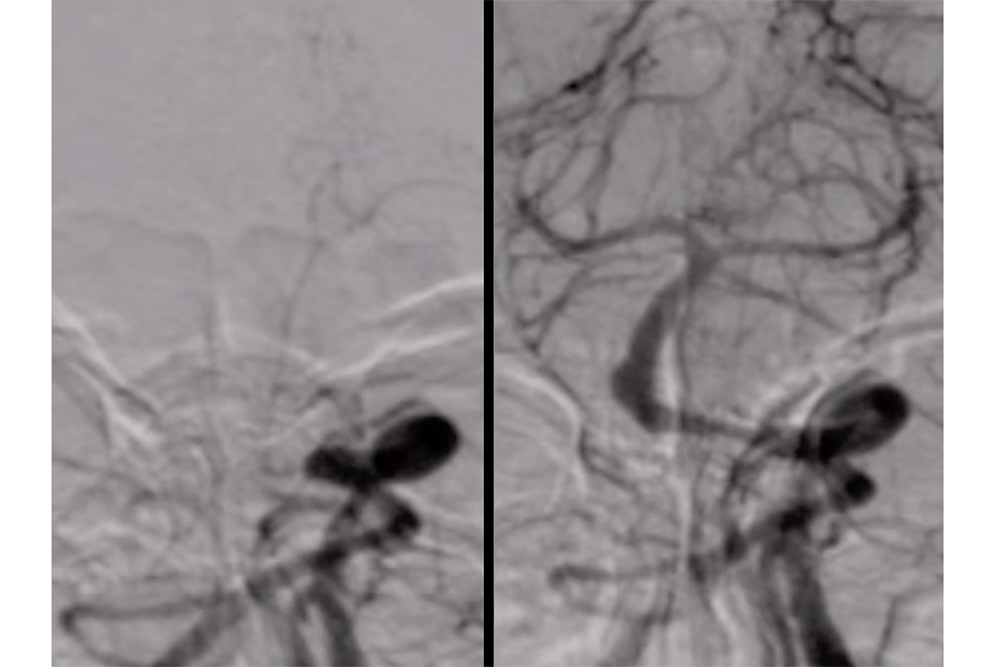

The procedure involves a catheter, just a few millimeters wide, that gets installed through the leg or wrist. It’s then fed inside the blood vessels to target clots in the brain, where doctors are able to physically remove the coagulated mass through the endovascular procedure.

Though strokes and aneurysms are different, the two can be treated similarly with new endovascular technology. Strokes are caused by blot clots in the brain which restrict blood flow, and aneurysms are formed when a blood vessel in the brain balloons and may eventually burst.